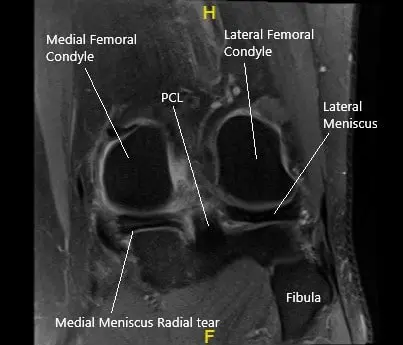

MRI of the left knee in the coronal section showing the torn medial meniscus.

MRI of the left knee suggested a tear of the posterior horn medial meniscus, notably with a radial component within the inner third, with meniscal extrusion into the medial gutter. There is tri-compartmental arthrosis, most pronounced over the patellofemoral compartment. Tendinosis of the extensor mechanism. Semimembranosus insertional tendinosis.